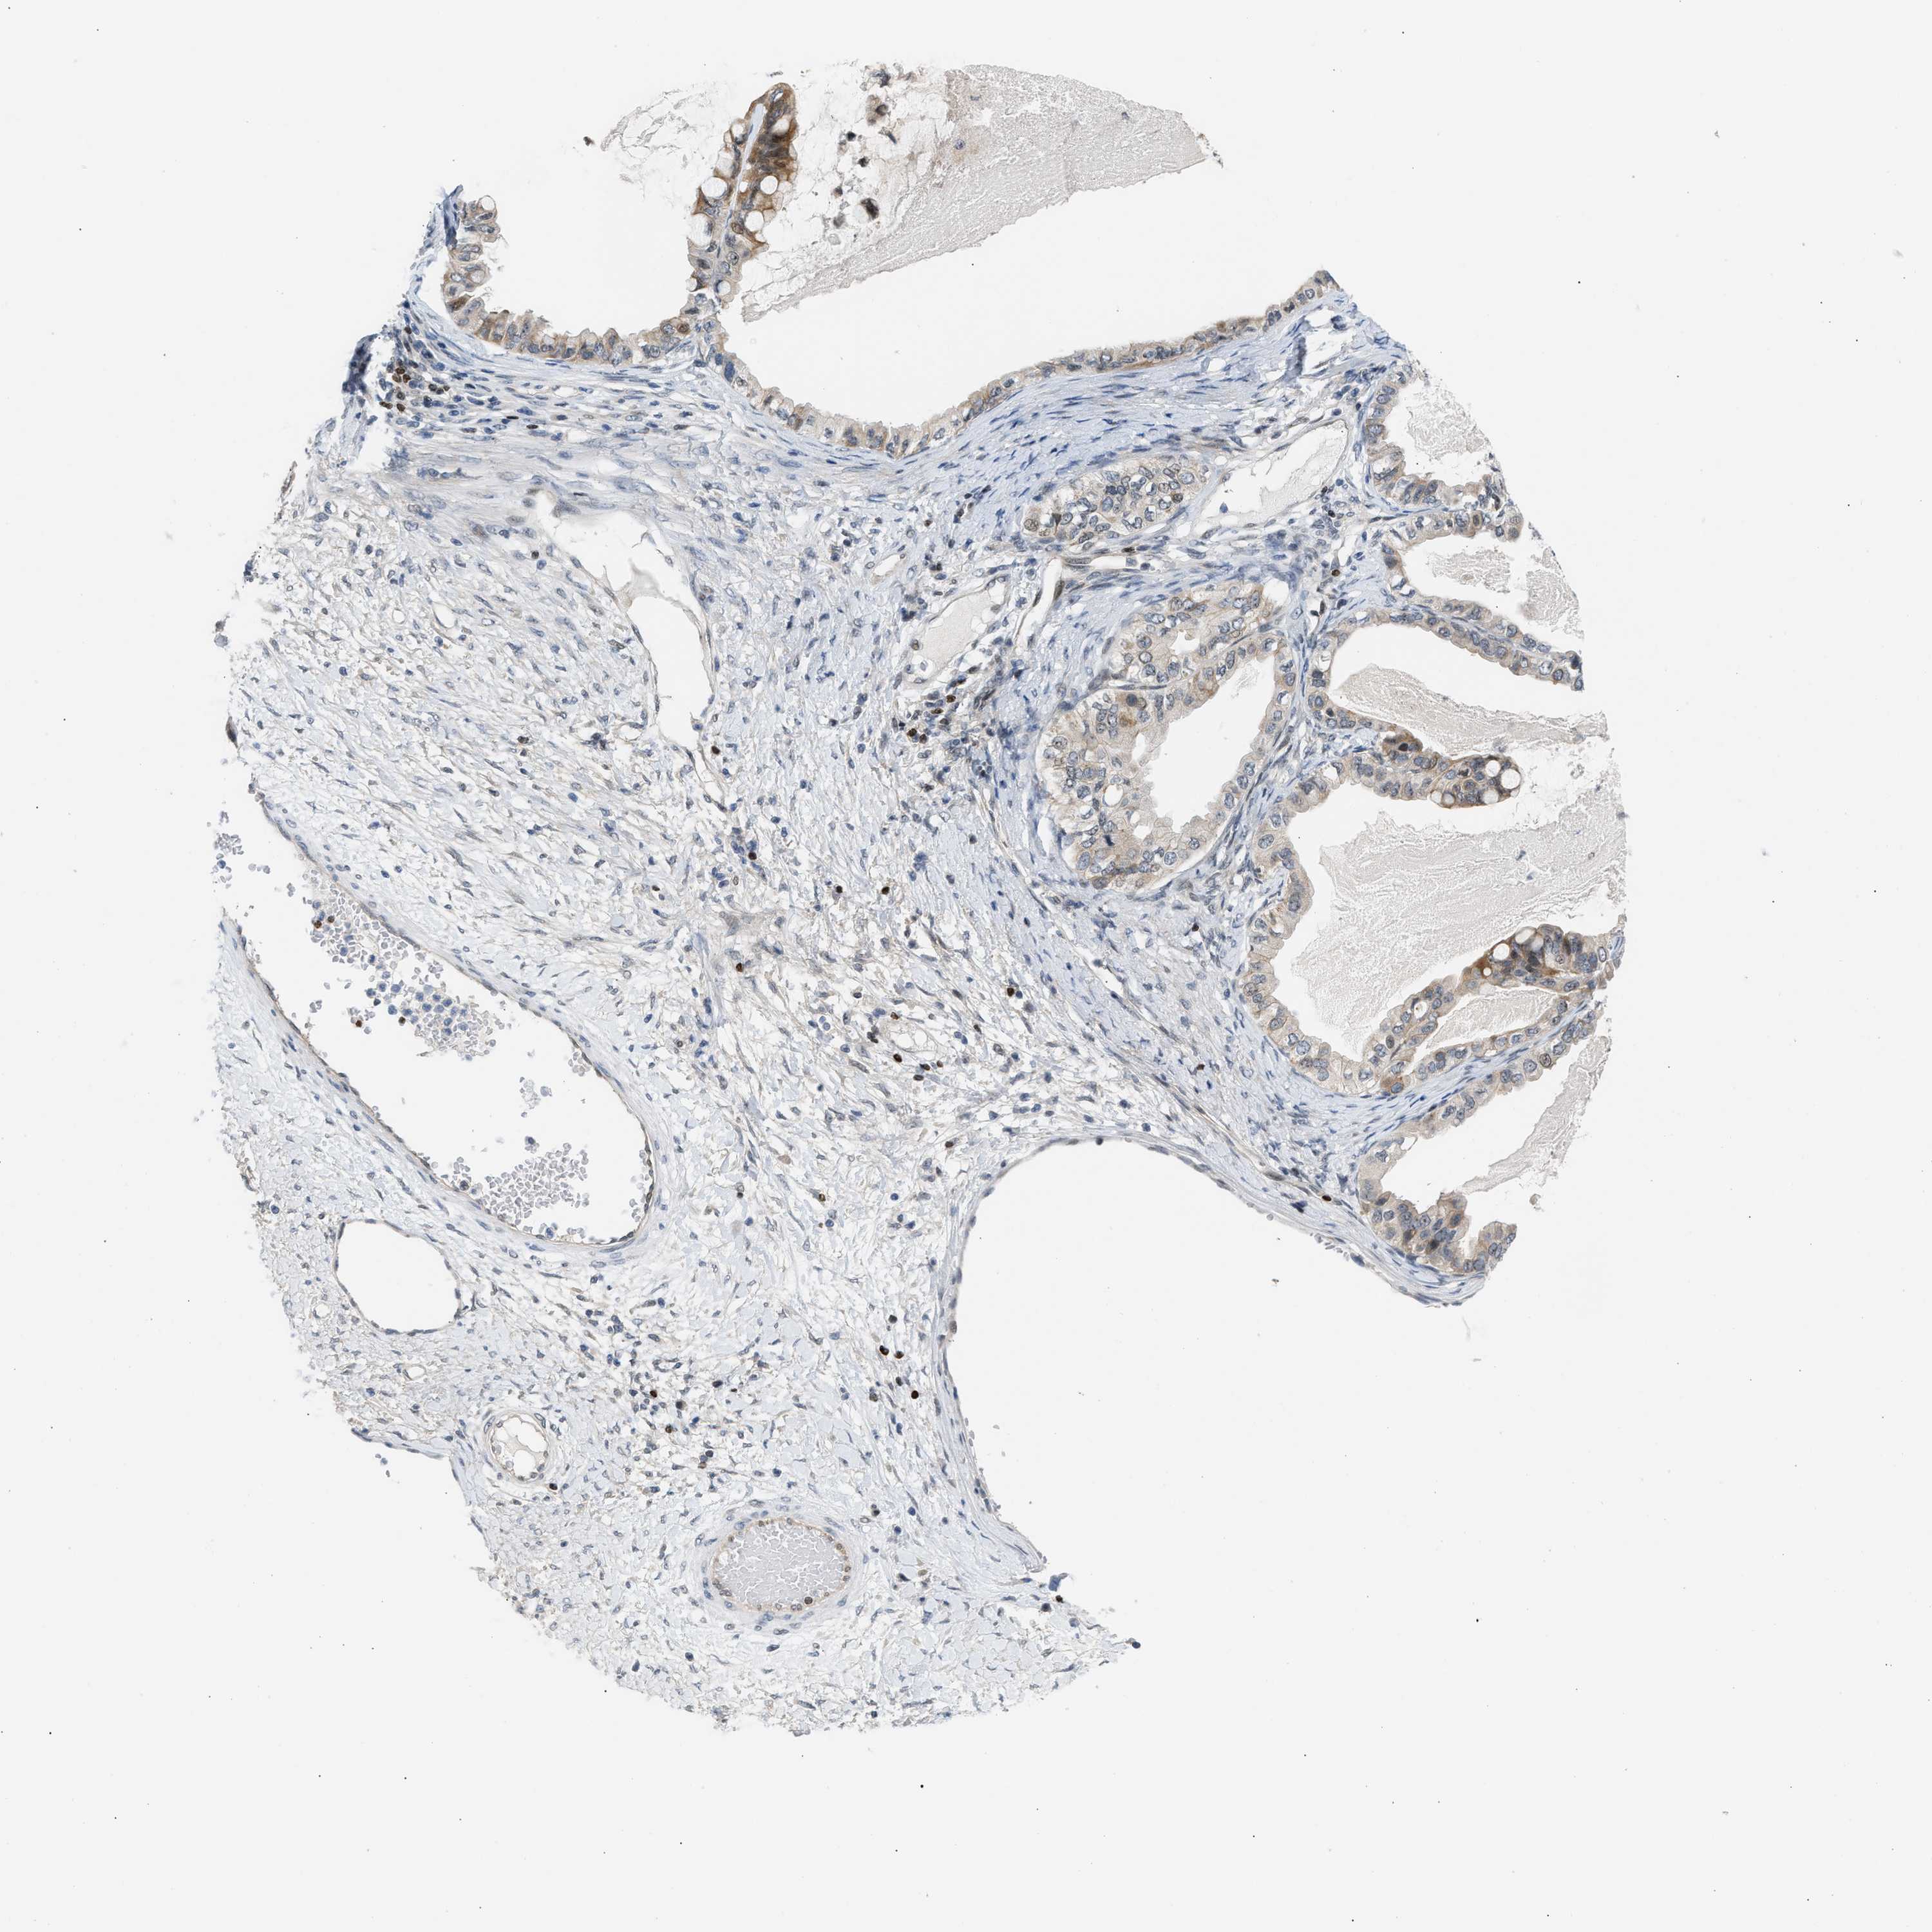

OVARIAN CANCER - Protein expressioni

A mouse-over function shows sample information and annotation data. Click on an image to view it in a full screen mode. Samples can be filtered based on level of antibody staining by selecting one or several of the following categories: high, medium, low and not detected. The assay and annotation is described here.

Note that samples used for immunohistochemistry by the Human Protein Atlas do not correspond to samples in the TCGA dataset.

Antibody stainingi

Antibody staining in the annotated cell types in the current human tissue is reported as not detected, low, medium, or high, based on conventional immunohistochemistry profiling in selected tissues. This score is based on the combination of the staining intensity and fraction of stained cells.

Each image is clickable and will lead to virtual microscopy that enables deeper exploration of all samples and also displays staining intensity scores, fraction scores and subcellular localization as well as patient and tissue information for each sample.

Antibody CAB020139

Staining

High

Medium

Low

Not detected

Intensity

Strong

Moderate

Weak

Negative

Quantity

>75%

75%-25%

<25%

None

Location

Nuclear

Cytoplasmic/membranous

Cytoplasmic/membranous,nuclear

Cystadenocarcinoma, serous, NOS

Carcinoma, endometroid

Cystadenocarcinoma, mucinous, NOS

Carcinoma, NOS